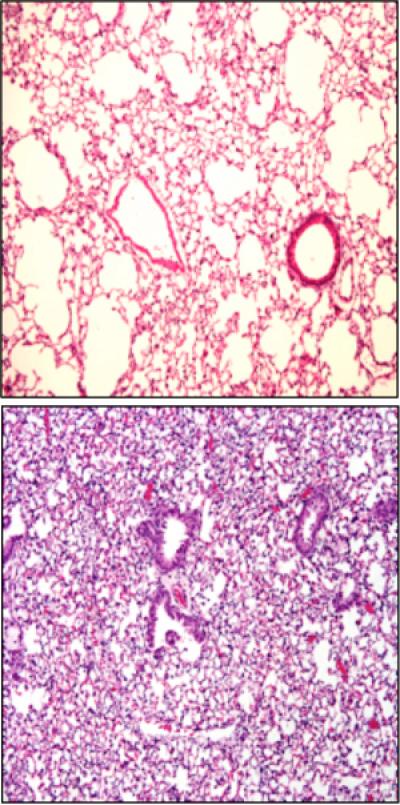

When the scientists transplanted healthy mouse lungs into mice that lacked bcl3 in their bone marrow, things went haywire. Without the gene, neutrophil production went unchecked, and the mice developed acute lung injury.

The investigators measured four times as many neutrophils in the blood of mice that lacked bcl3 compared with normal mice. The bcl3 gene, they showed, acts like a master switch to control the effects of G-CSF on neutrophil production.